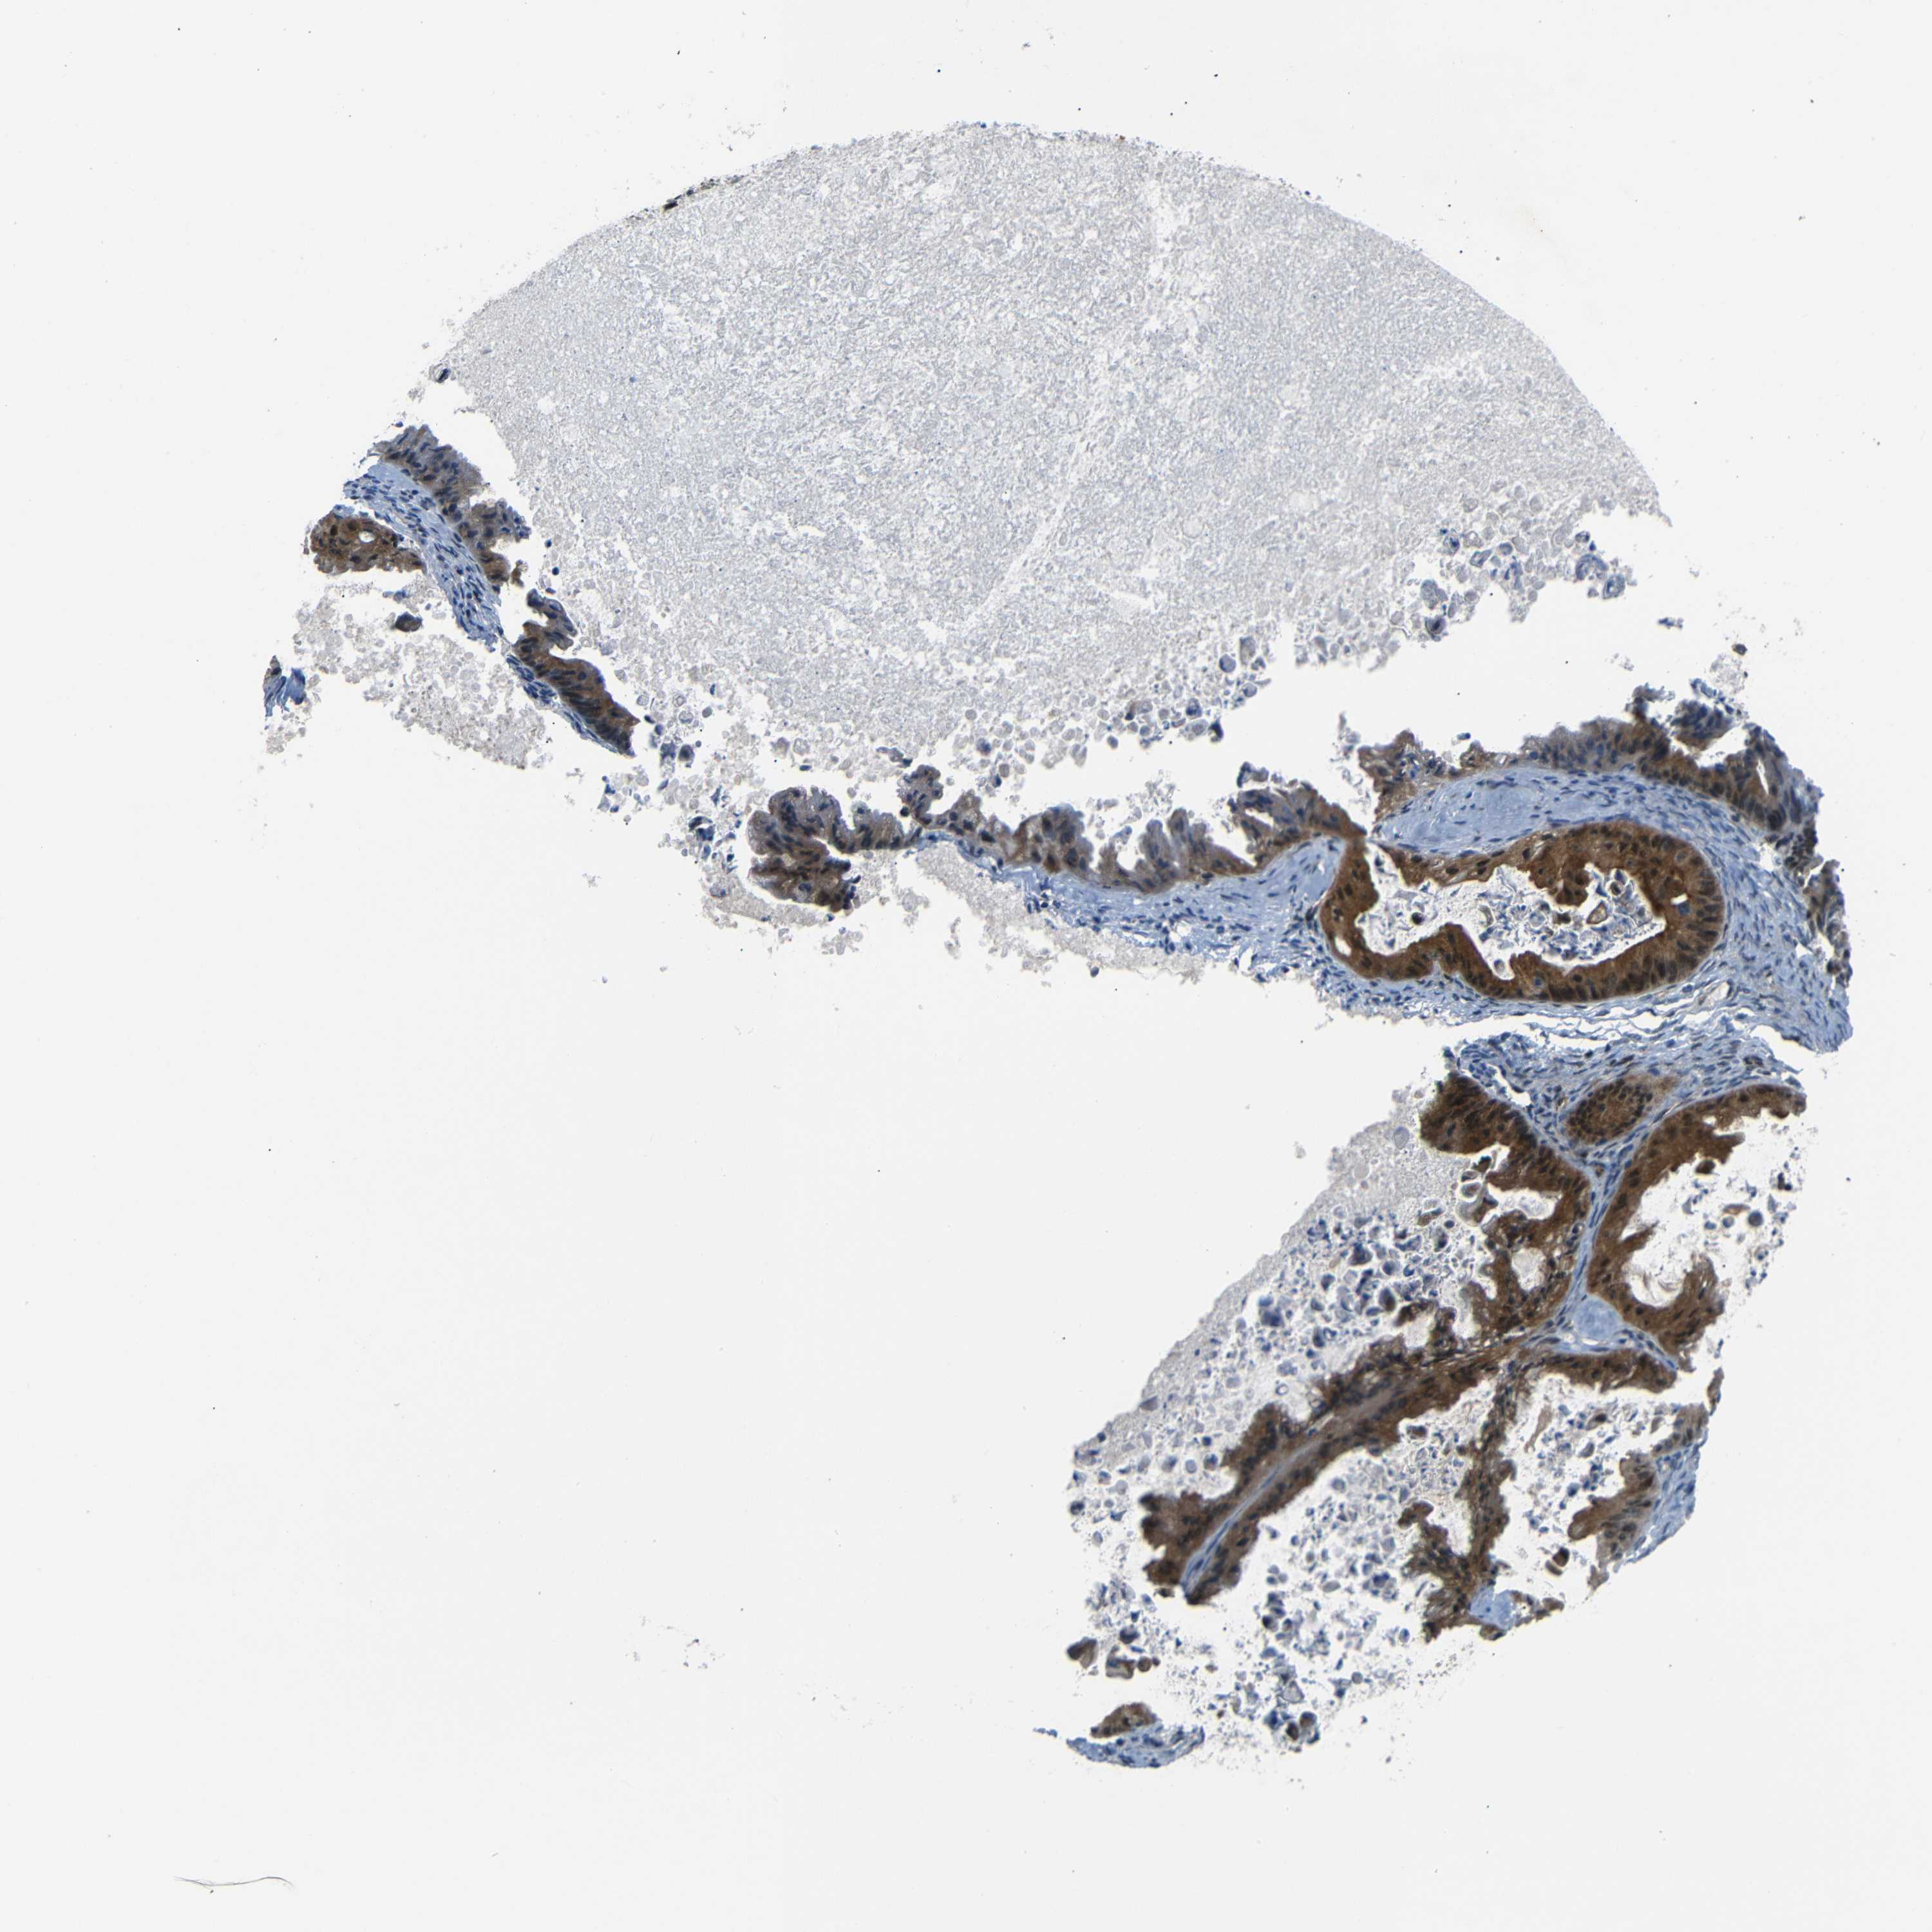

OVARIAN CANCER - Protein expressioni

A mouse-over function shows sample information and annotation data. Click on an image to view it in a full screen mode. Samples can be filtered based on level of antibody staining by selecting one or several of the following categories: high, medium, low and not detected. The assay and annotation is described here.

Note that samples used for immunohistochemistry by the Human Protein Atlas do not correspond to samples in the TCGA dataset.

Antibody stainingi

Antibody staining in the annotated cell types in the current human tissue is reported as not detected, low, medium, or high, based on conventional immunohistochemistry profiling in selected tissues. This score is based on the combination of the staining intensity and fraction of stained cells.

Each image is clickable and will lead to virtual microscopy that enables deeper exploration of all samples and also displays staining intensity scores, fraction scores and subcellular localization as well as patient and tissue information for each sample.

Antibody HPA013328

Staining

High

Medium

Low

Not detected

Intensity

Strong

Moderate

Weak

Negative

Quantity

>75%

75%-25%

<25%

None

Location

Nuclear

Cytoplasmic/membranous

Cytoplasmic/membranous,nuclear

Cystadenocarcinoma, serous, NOS

Carcinoma, endometroid

Cystadenocarcinoma, mucinous, NOS

Carcinoma, NOS